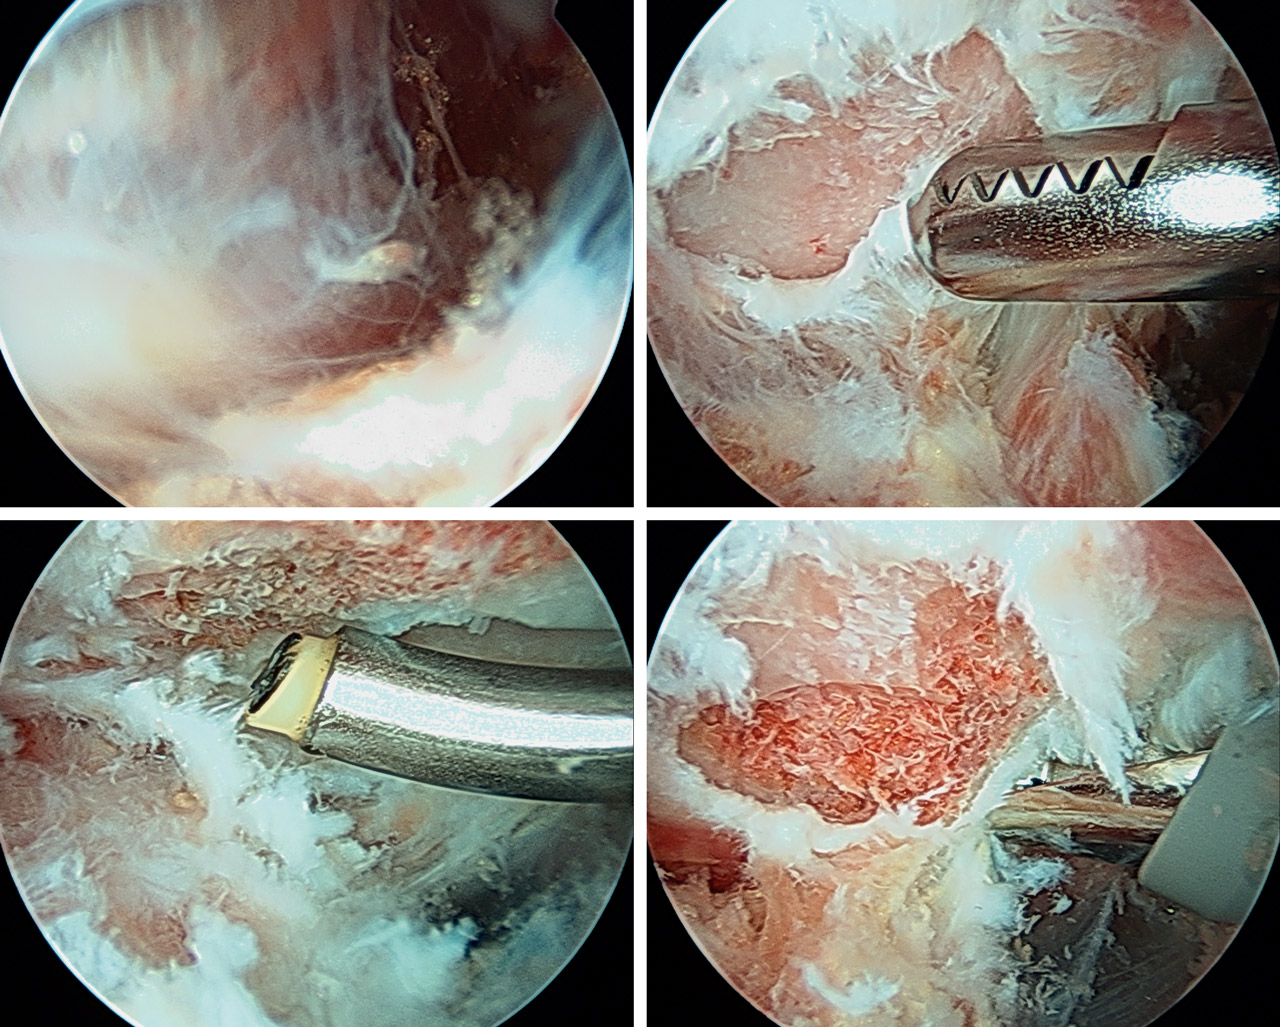

A través del portal de trabajo y con ayuda de sinoviotomo y radiofrecuencia, se procedió a la extirpación del tejido fibroso y bursal para exponer el ángulo superomedial de la escápula, localizado mediante palpación directa y la movilización indirecta de la escápula al mover el brazo (Figura 4).

En todos los casos se realizó extirpación parcial del ángulo superomedial de la escápula mediante fresa de 4 mm de diámetro, con unas dimensiones aproximadas de 2 cm en el plano anteroposterior y 2 cm en el plano mediolateral (Figura 5). Para el cierre de los portales se utilizó un monofilamento.